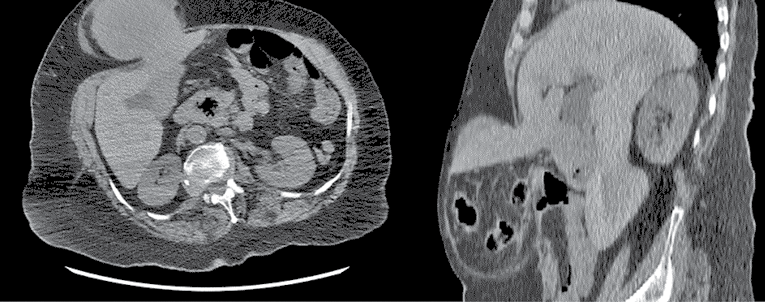

A 74-year-old woman with a BMI of 26.56 kg/m2, presented to the emergency department with pain and swelling in the epigastric region. She had no history of previous surgery and was only diagnosed with hypertension. Physical examination revealed an unreducible hernia defect in the epigastric region. Her vital signs included a blood pressure of 130/90 mmHg, a heart rate of 80 beats/minute and a respiratory rate of 18 breaths/minute. The patient was diagnosed with an irreducible epigastric hernia and hospitalized in the clinic. Computed tomography (CT) revealed that the hernia defect included the transverse colon, omentum and liver segment 3 (Figure 1). The laboratory findings of the patient included a white blood cell count of 6.83 × 103/µL, alanine aminotransferase level of 68 IU/L, aspartate aminotransferase level of 51 IU/L and C-reactive protein level of 1.41 mg/L.

Figure 1. Preoperative computed tomography images